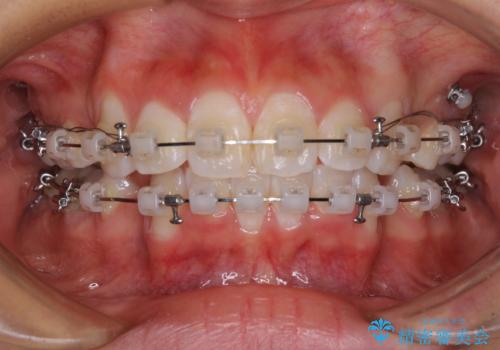

- クリアブラケット

- 1年7ヶ月

治療前の上下正中はずれていましたが、骨格的な上下左右差はあまり認められなかったため、正中を揃えて治療を終えることができました。

1年半ほどで治療を終えることができるとは我々も想像しておらず、患者様には大変満足していただきました。